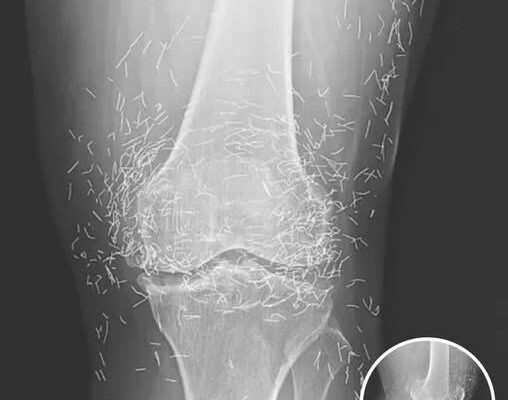

A X-ray of the patient’s knee showing acupuncture needles embedded in the tissue, Photo Credit: Reddit

As for the South Korean woman, her case was recently documented in the New England Journal of Medicine. While the needles may have been intended to help, her X-rays tell a cautionary tale about the potential risks of extreme alternative therapies.

A routine X-ray revealed an unexpected surprise when doctors examined the knees of a 65-year-old woman suffering from severe joint pain. What they found was nothing short of astonishing — hundreds of tiny gold needles embedded deep in her tissue.

There are other complications as well. Needles lodged in tissue can interfere with medical imaging. “They can obscure parts of the anatomy on an X-ray,” Guermazi noted. Even more alarming, patients with metal fragments in their bodies should never undergo an MRI, as the magnetic force could cause the needles to move — potentially puncturing blood vessels and causing life-threatening damage.